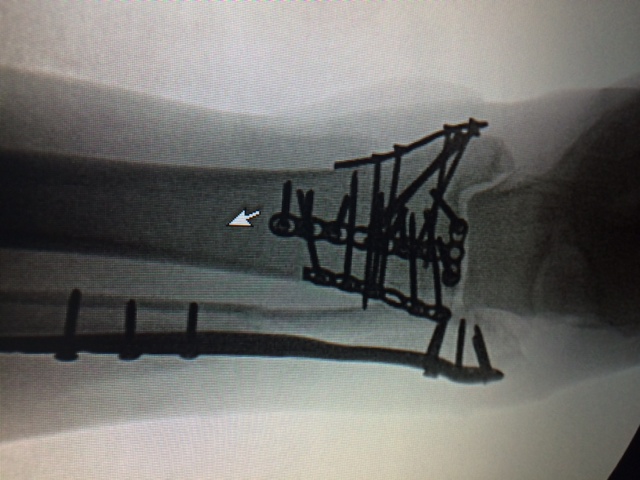

Aug. 29th, 2014...Hit head on by a car going 40 mph while on my bicycle in Copake Lake, NY. I suffered a shattered left knee cap, pylon/trimellioar fracture of the right ankle, and a fractured right hand.

3 surgeries (Dr. Wellman - Knee, Dr. Helfet - Ankle, Dr. Fufa - Hand ... fondly designated the "dream team."), and 4 weeks in HSS later, I was released. I was non-weight bearing on my right ankle, left knee in a thigh to ankle locked straight leg, and a splinted/bandaged non-usable right hand. I left on a customized walker that used my right forearm as my right leg. Steps of any kind were out of the question. I forgot to mention we sold our home the week before, and were expected to be out within 30 days.